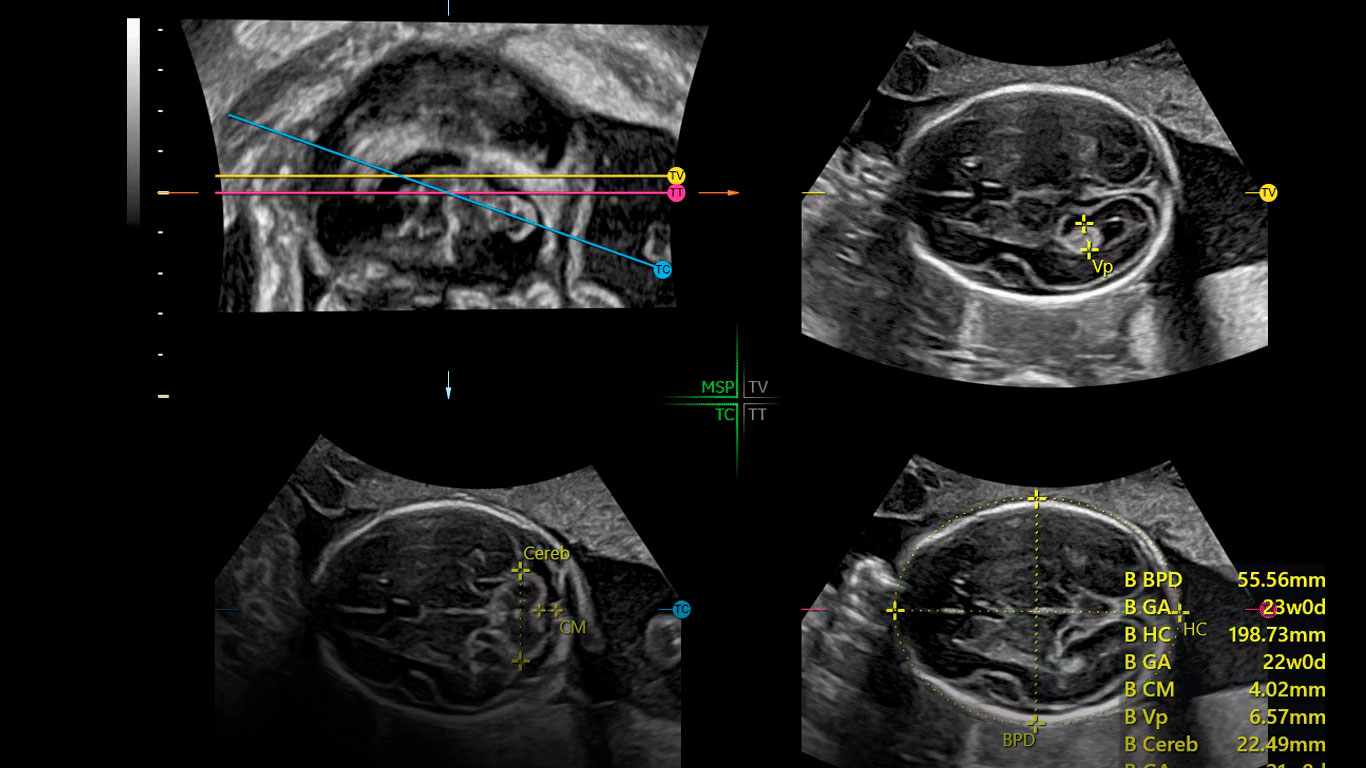

El sistema Voluson Expert 20 le ayudará a responder a cuestiones relevantes con imágenes de última generación para agilizar la evaluación y el diagnóstico. Ahorre un tiempo valioso con la inteligencia artificial (IA) y las herramientas de automatización que ayudan a descubrir nuevas eficiencias en cada paso.

“Estos equipos tienen múltiples recursos que realmente me permiten, no solo cumplir con las expectativas diagnósticas de los colegas, sino siempre ir un poco más allá”.

Dr. Juan Fajardo

Radiólogo

«Los avances que se han conseguido en los Voluson en los últimos años son muy elevados y eso permite unos diagnósticos precisos y un manejo más amigable para el profesional».

Dr. Eduard Gratacós

Ginecobstetra